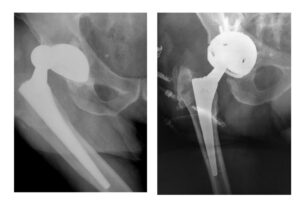

Στην  εικόνα 5 βλέπουμε ένα χαρακτηριστικό παράδειγμα από περιστατικό μας με σοβαρή ανατομική ανωμαλία, αποτέλεσμα βαριάς δυσπλασίας του ισχίου (DDH). Η τρισδιάστατη αξονική μάς επέτρεψε να κάνουμε ακριβείς μετρήσεις και λεπτομερή σχεδιασμό του χειρουργείου μας

Στην εικόνα 16 παρουσιάζεται ο σχεδιασμός   της αρθροπλαστικής σε περιστατικό της κλινικής μας: επάνω αριστερά η ανατομία του ισχίου πριν την επέμβαση, κάτω αριστερά η εικονική εμφύτευση της  κοτύλης. Επάνω δεξιά η εικονική εμφύτευση του μηριαίου στυλεού. Τέλος, κάτω δεξιά το “πάντρεμα”των δύο και το τελικό αποτέλεσμα.

Στην εικόνα 17, οι ενδείξεις της οθόνης  από το χειρουργείο της ίδιας ασθενούς, όσον αφορά τη θέση των εμφφυτευμάτων και η ακτινολογική επιβεβαίωση κατά τη διάρκεια της επέμβασης. Το αποτέλεσμα ήταν προβλέψιμο και άριστο